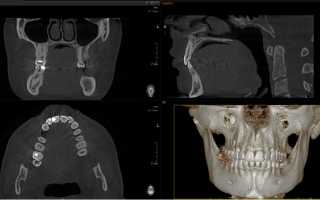

Конусно-лучевая компьютерная томография позволяет в трехмерном изображении обследовать зубы с челюстью и предоставляет высококачественный цифровой снимок, который нужен для диагностики зубочелюстной системы, а также составления предстоящей лечебной терапии.

Конусно-лучевая томография челюстно-лицевого аппарата на сегодняшний день считается наиболее достоверной процедурой в сфере стоматологии, потому что дает возможность верно установить диагноз, а также подобрать и объяснить пациенту соответствующий метод лечения.

- Полная информативность. Благодаря уникальным функциональным возможностям аппарата специалист может обследовать диагностический снимок в любом сечении и проекции, а также определить особенности анатомии челюстно-лицевого аппарата.

- Скорость. Диагностика проводится в течение нескольких секунд. На протяжении данного периода времени система создает объемную 3D модель всего челюстно-лицевого аппарата.

- Точность. Созданную трехмерную модель допустимо смотреть и вращать под разным углом, в отличие от обследования в режиме 2D. При этом можно сделать съемку зубочелюстной системы, а также создать 3D модель для одиночной реставрации.